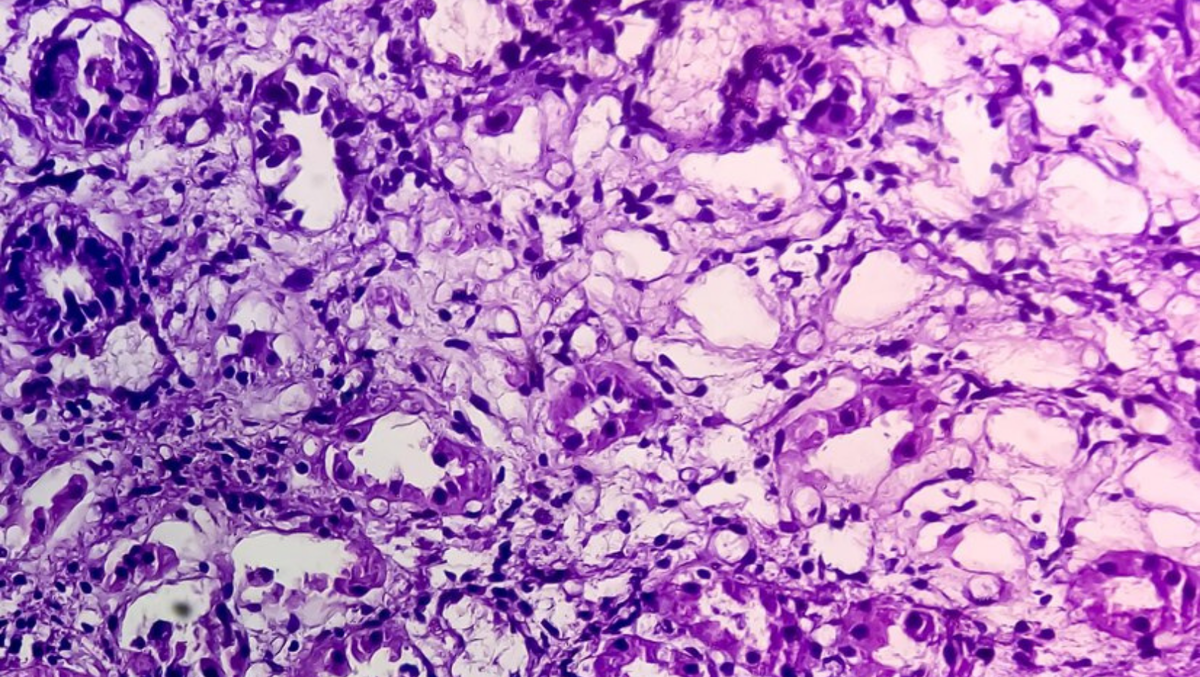

Гистологический слайд образца ткани под микроскопом